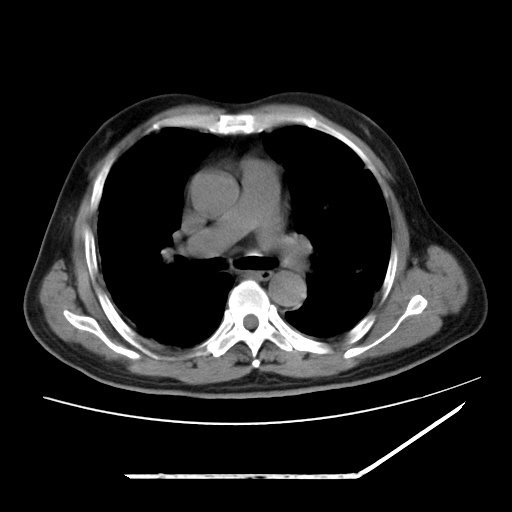

男,57,畏寒,发热

两肺野多发大小不一高密度灶,纵膈内见肿大淋巴结,要考虑转移瘤可能。双侧胸腔少量积液。

双肺多发结节样病灶,部分内见透光区,纵隔内见淋巴结肿大。结核临床如有畏寒,高热,白细胞增高首先考虑迁徙性肺脓肿(多是金黄色葡萄球菌感染)。

注意除外转移瘤。